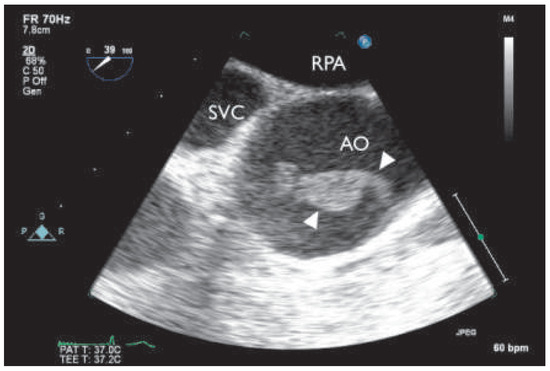

An Unusual Cause of Thromboembolic Disease

by Marc L. Fischer, Peter Matt, Beat A. Kaufmann and Arnheid Kessel-Schaefer

Cardiovasc. Med. 2015, 18(7-8), 229; https://doi.org/10.4414/cvm.2015.00348 - 12 Aug 2015

Cited by 1 | Viewed by 160

Abstract

The most frequent noncardiac sources of systemic embolism are mural thrombi within proximal aneurysms, ulcerated atherosclerotic plaques, and paradoxical emboli originating from the venous side of the circulation [...] Full article

Figure 1